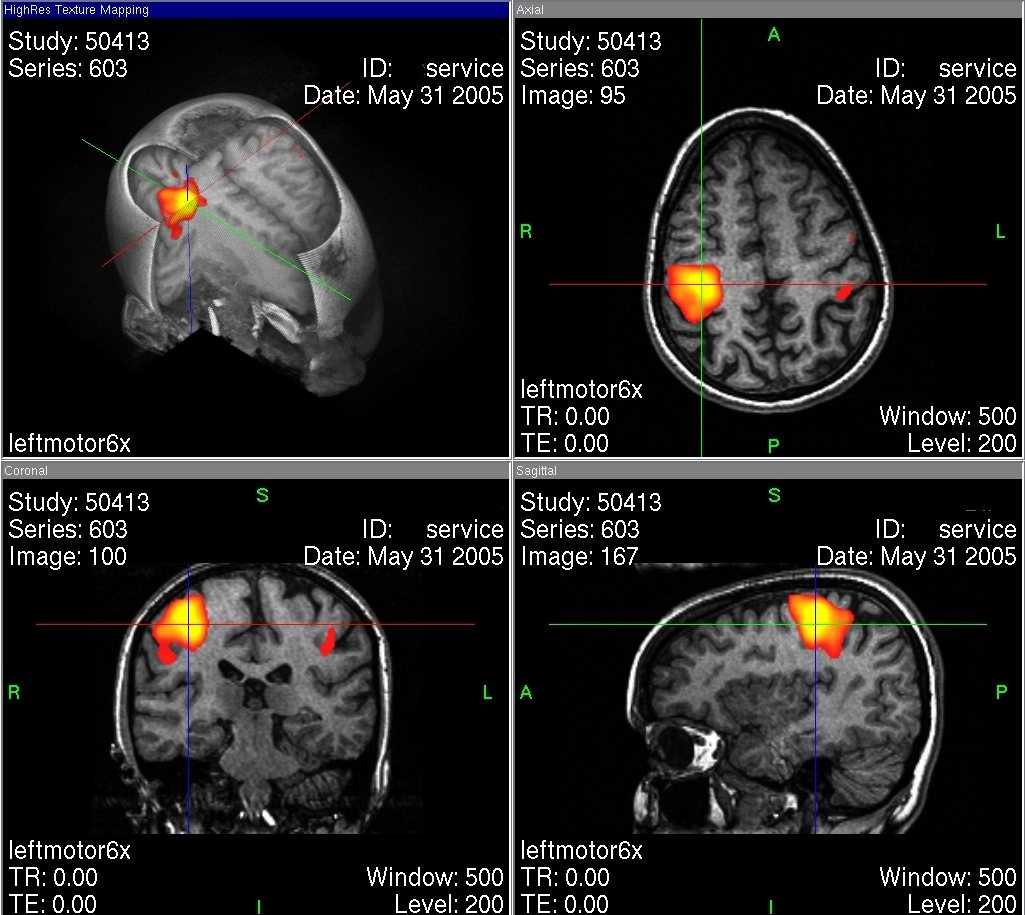

Mit neueren Methoden der Neurowissenschaften können die Fähigkeiten unseres Gehirns immer genauer untersucht werden. Ein Blick ins Gehirn ist mit bildgebenden Verfahren wie der Computertomographie (CT) oder der Magnetresonanztomographie (MRT) möglich. Die funktionale Magnetresonanztomographie (fMRT) kann Änderungen in der Durchblutung von Hirnarealen und damit nicht nur die Struktur, sondern auch die Aktivierung sichtbar machen. So wird das neuronale Netz im Gehirn in seiner Funktion indirekt erfassen. Auf diese Weise hofft man besser zu verstehen, wie unser Gehirn funktioniert und lernt. Allerdings sind die bisherigen Erkenntnisse über die Funktionsweise des Gehirns beim Lernen aus verschiedenen methodischen Limitierungen sehr begrenzt und so bleibt dieses Thema eine große Herausforderung für die Hirnforschung.

Übersicht der verschieden Beobachtungsebenen einer fMRT-Aufnahme nach linksseitigem „Finger-Tapping“. Die farbig dargestellten Bereiche symbolisieren einen erhöhten Stoffwechsel und somit eine Hirnaktivität. Je weiter die Farbe ins Gelbliche abweicht, desto wahrscheinlicher ist Aktivität

https://commons.wikimedia.org/wiki/File:Fmrtuebersicht.jpg M.R.W.HH at German Wikipedia, Public domain, via Wikimedia Commons